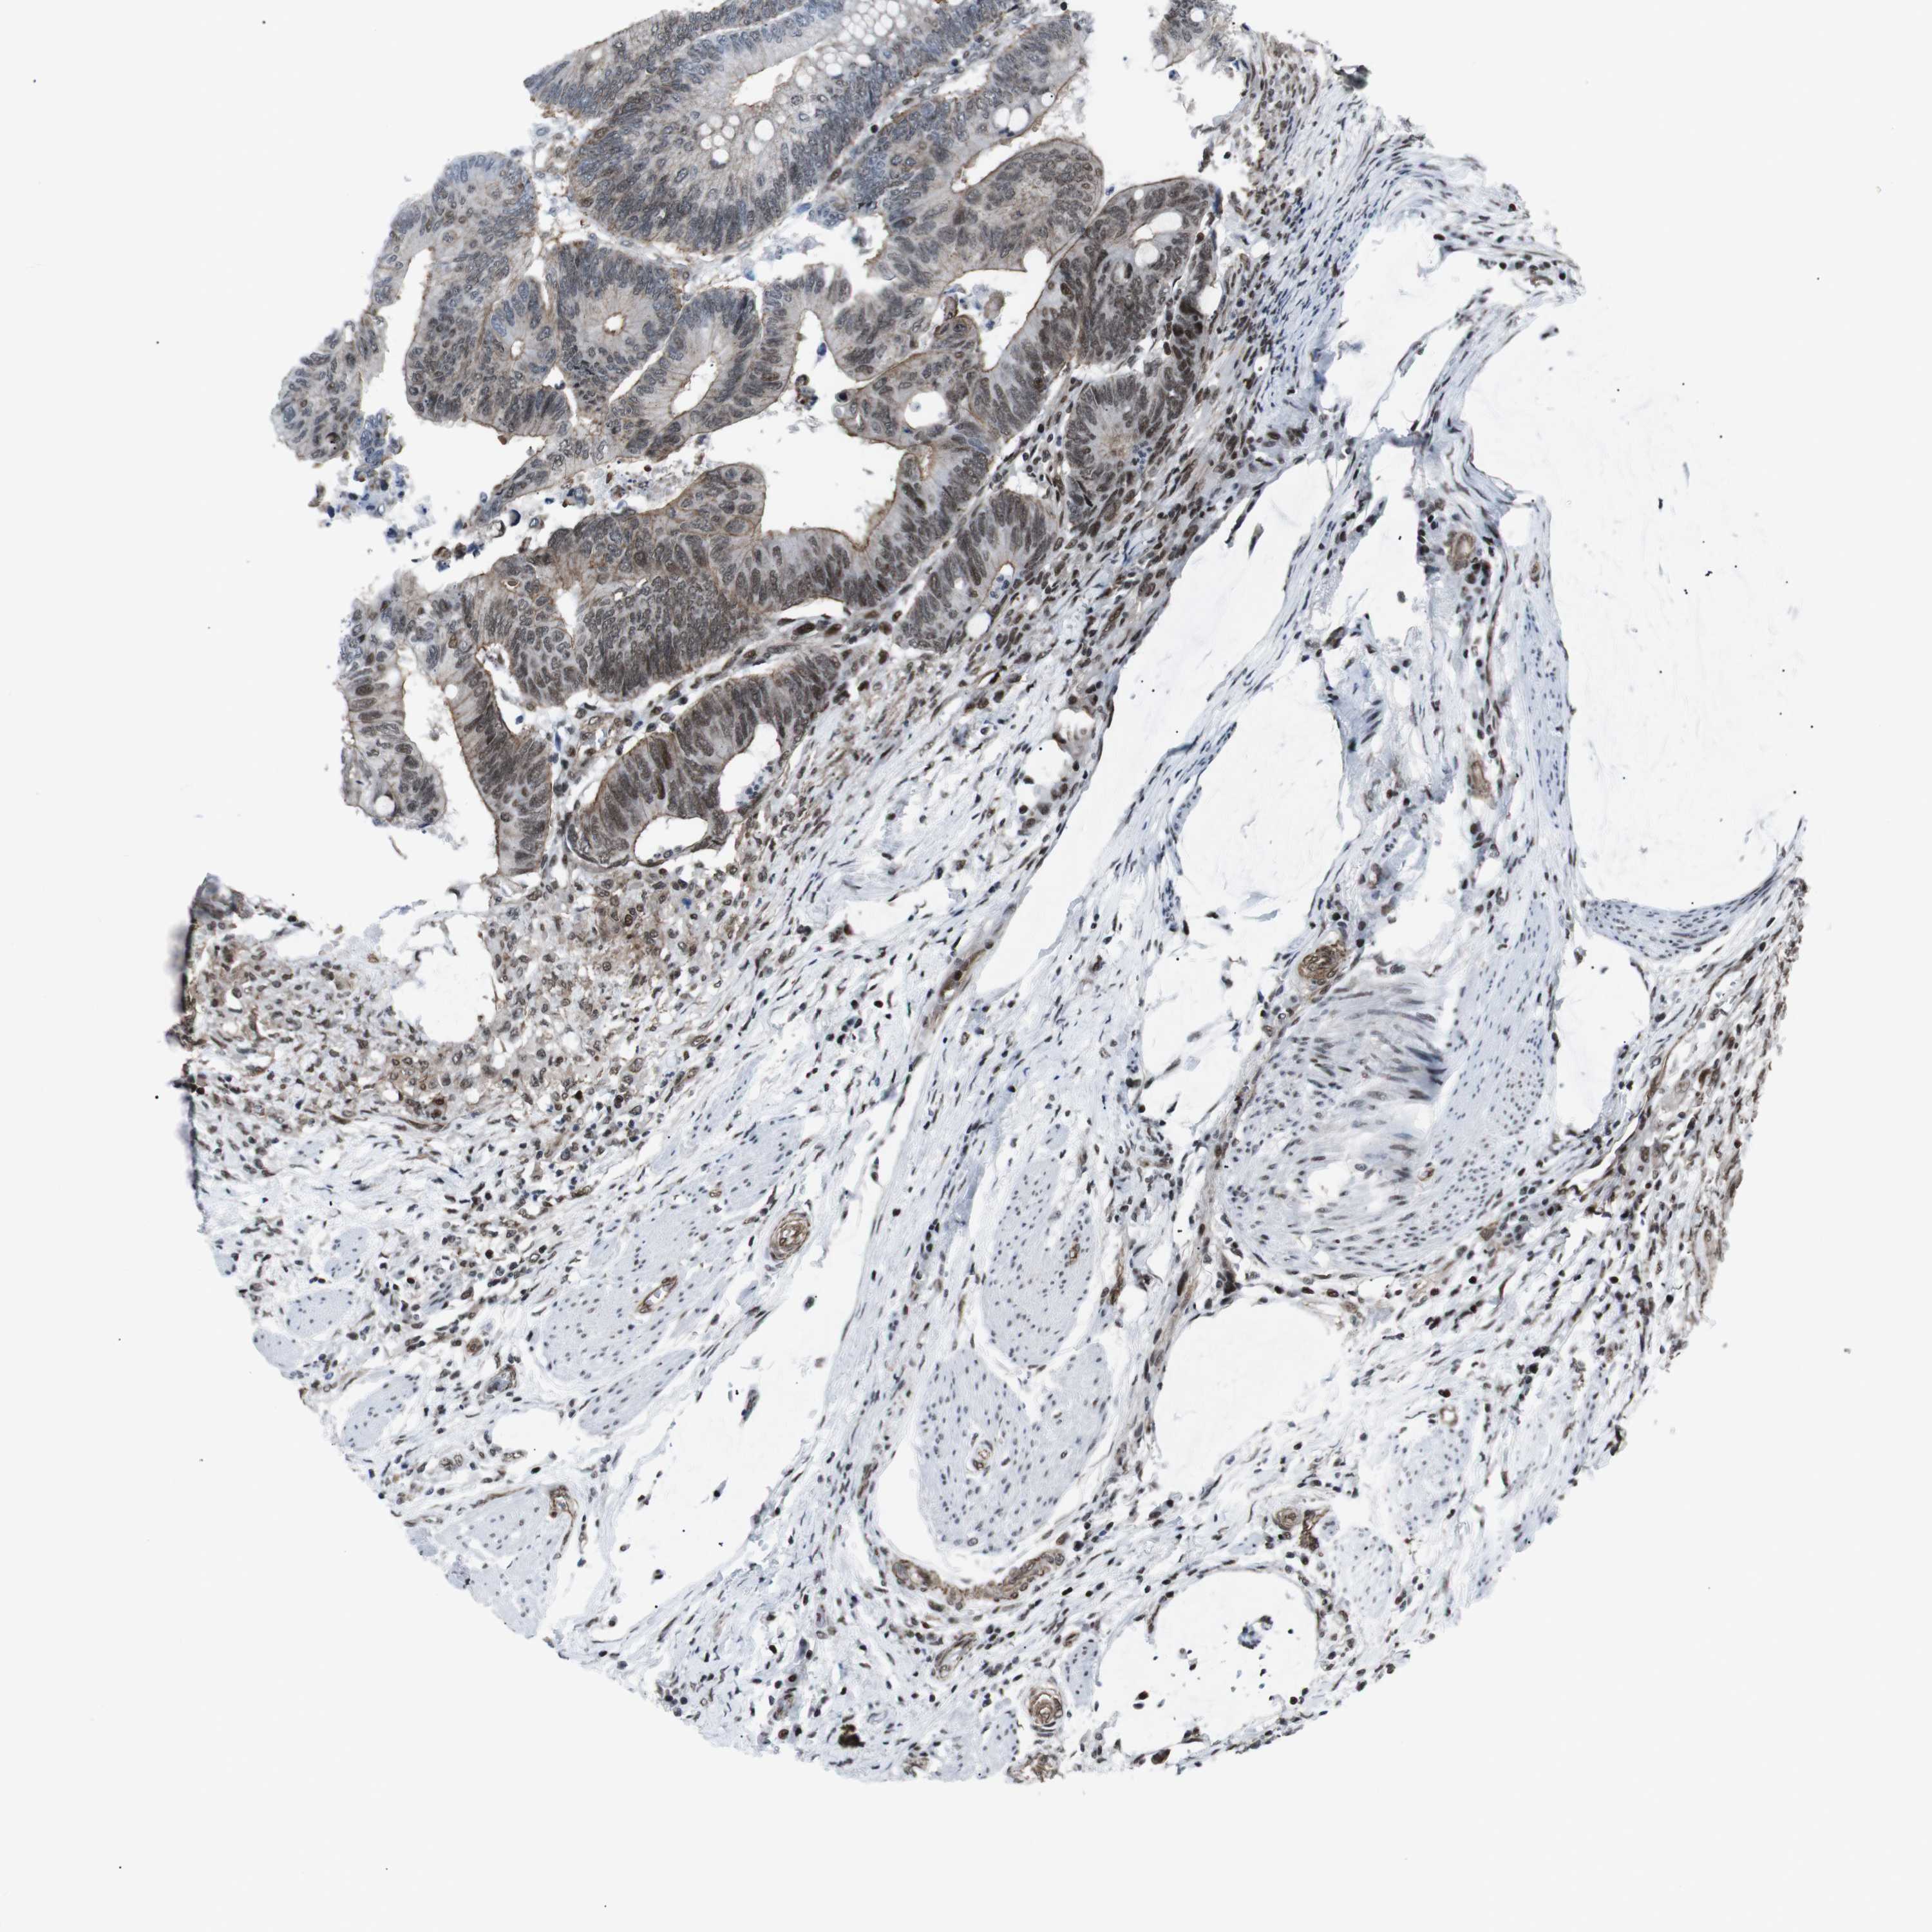

CANCER COLORECTAL CANCER Show tissue menu

Colorectal cancer

Human cancer

Rectum adenocarcinoma